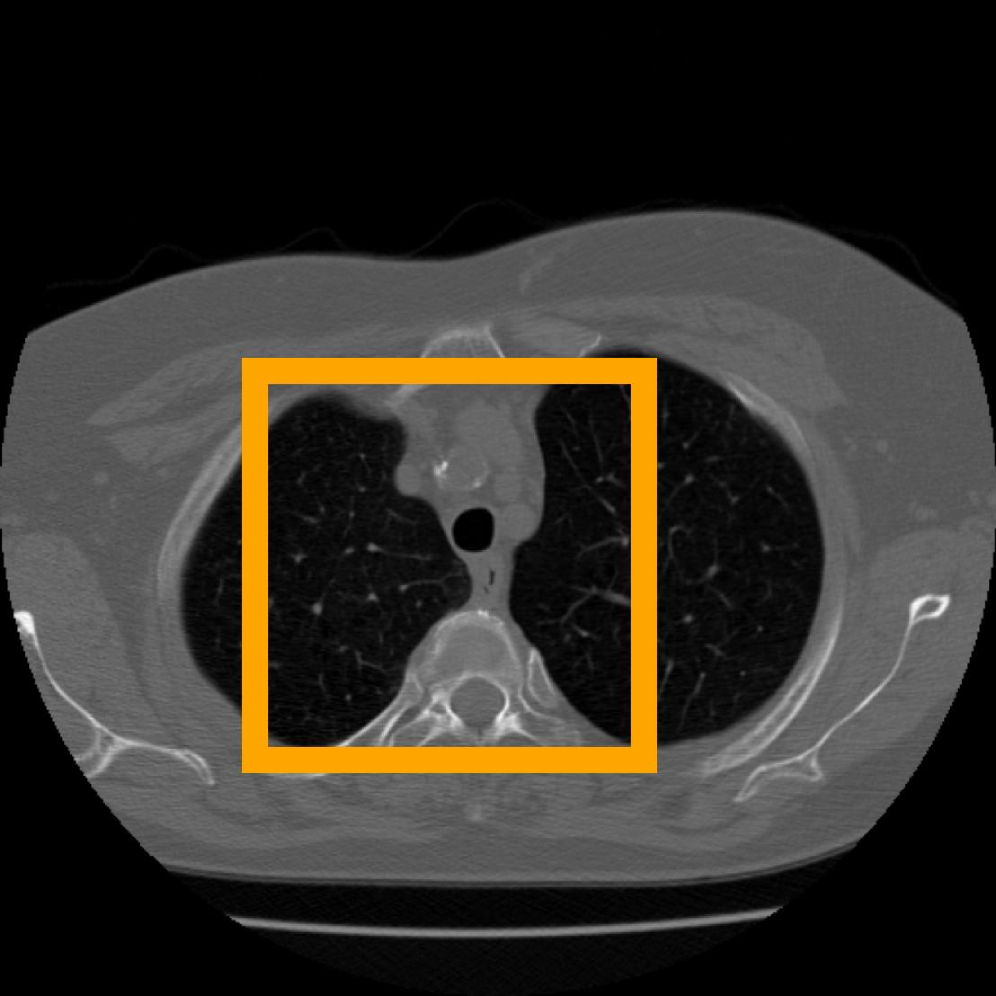

Figure 10: The visual comparison of different compression methods on a CT Heart Segmentation image.

Figure 11: Zoomed-in view of the highlighted region in Figure 10.

IV-B3 Visual Comparison

Figures 7 and 8 present representative examples from the CIL dataset and their zoomed-in regions, respectively. For the CT Heart Segmentation dataset, Figures 10 and 12 illustrate typical reconstruction results, while Figures 11 and 13 further enlarge local regions to compare structural details. Across both datasets, COLI preserves fine structures and global continuity well even at relatively low bpp. Specifically, on the CIL dataset, COLI attains the lowest bitrate among INR-based methods while still maintaining clear texture details. On the CT Heart dataset, COLI also operates at a low bpp within the INR family and delivers superior visual quality with improved detail fidelity and smoother structural presentation. The zoomed-in regions show fewer blocking artifacts and smoother transitions, making COLI especially suitable for large images and medical images. These visual results validate that INR-based compression can achieve efficient storage with reliable perceptual consistency, offering practical advantages for real-world large-scale image processing.